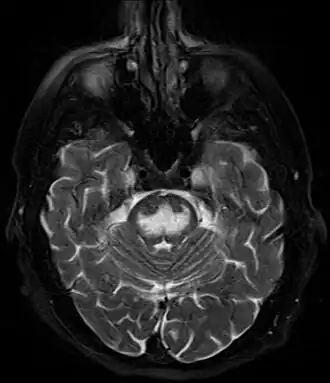

| Imagem axial ponderada em T2 com saturação de gordura mostrando hiperintensidade na ponte com preservação das fibras periféricas. O paciente era alcoólatra e foi internado com Na sérico de 101, tratado com solução salina hipertônica, e ficou com quadriparesia, disartria e estado mental alterado. | |

Pode ser diagnosticado clinicamente no contexto apropriado, mas pode ser difícil de confirmar radiologicamente usando técnicas de imagem convencionais. As alterações são mais proeminentes na ressonância magnética (RM) do que na tomografia computadorizada (TC), mas geralmente levam dias ou semanas após o início dos sintomas agudos. A imagem por RM normalmente demonstra áreas de hiperintensidade em imagens ponderadas em T2.[29]